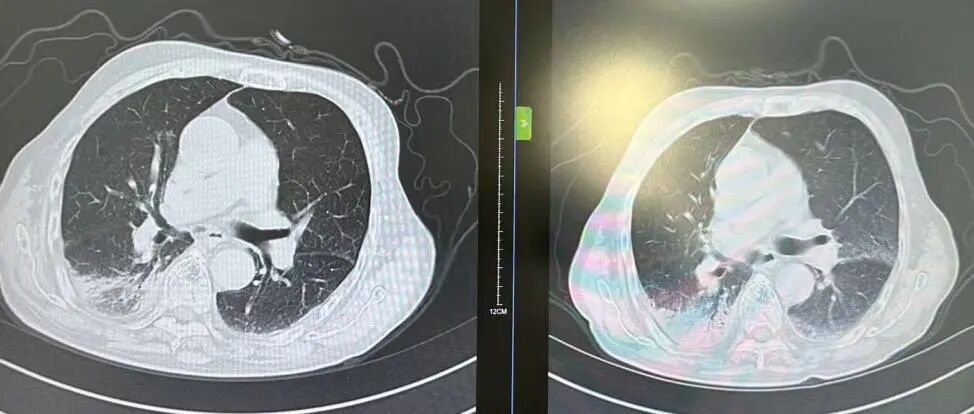

内容提要 近日,市第二人民医院呼吸与危重症医学科宋刚主任团队,成功救治一名98岁高龄、患有罕见隐源性机化性肺炎(COP)的患者。面对高龄、病情复杂、诊治风险高等重重困难,团队凭借精湛医术与丰富经验,帮助老人转危为安,再次彰显了科室在危重症救治领域的强大实力。 挑战一:高龄禁区,敢为人先 患者因发热、咳嗽,伴乏力、气短、喘息等症状来院,此前在当地诊所使用多种抗生素均无效,病因成谜。要明确诊断,支气管镜检查是关键一步,但对近百岁老人而言,此项操作犹如踏入“生命禁区”,风险极高。宋刚主任团队没有退缩,在全面评估、周密预案、充分沟通的基础上,凭借丰富经验成功实施检查,为后续治疗打开了至关重要的突破口。 治疗前患者肺部CT影像 挑战二:罕见病症,迷雾重重 检查结果指向一种罕见疾病——隐源性机化性肺炎(COP)。此病本就少见,好发于50~60岁人群,在近百岁老人中发生更是极为罕见。更为棘手的是,患者还伴有胸腔积液。COP通常表现为发热和肺部影像上的“游走性”阴影,很少合并胸腔积液,这使得诊断工作如雾里看花,难度倍增。 挑战三:病菌分辨,生死抉择 诊断刚明,新的考验接踵而至:患者标本中检出了根毛霉菌。COP的核心治疗是糖皮质激素,若根毛霉菌是致病菌,激素可能引发真菌扩散,用药无疑将导致致命风险。因此,辨别其是“定植菌”还是“致病菌”,成为治疗成败的关键。 宋刚主任团队凭借丰富的临床经验和严谨的诊疗思维,结合患者肺部影像特征、症状及化验结果,综合判断认为该霉菌属于定植菌,从而排除了治疗障碍,确保了后续用药安全。 精心施治,百岁老人转危为安 在后续治疗中,团队如履薄冰,精细平衡抗凝与激素治疗带来的出血、感染等风险,制定个体化方案。经过精心治疗与护理,老人肺部病灶显著吸收,各项指标恢复正常,最终康复出院。 治疗前后肺部CT影像对比,左侧为治疗后,右侧为治疗前。 此次成功救治,充分体现了市二院呼吸与危重症医学科在复杂疑难呼吸道疾病及危重症领域的综合救治能力。面对高龄高风险患者,团队始终以患者为中心,在风险与疗效间精准把握,用技术与责任守护每一位患者的呼吸健康。 人民医院 人民名医 宋刚 主任医师 ·葫芦岛市第二人民医院呼吸与危重症医学科主任 ·辽宁省生命科学学会东北呼吸与危重症医学(PCCM)分会辽宁省基层委员会副主任委员 ·辽宁省细胞生物学学会放射粒子治疗专业委员会理事 ·辽宁省抗击新冠肺炎疫情先进个人 ·辽宁省预防医学会第一届吸烟相关疾病防治专业委员会委员 ·葫芦岛市劳动鉴定委员会专家库成员 ·葫芦岛市医学会呼吸内科学分会第三届委员会副主任委员 专业特色:擅长呼吸系统疑难及急危重患者的救治,如急慢性支气管炎、支气管哮喘、慢性阻塞性肺疾病、肺炎、肺栓塞、肺癌、间质性肺疾病、睡眠呼吸暂停综合征等,尤其擅长有创无创机械通气、支气管镜下相关检查及治疗(TBNA、气道支架置入术、球囊扩张等)、全肺灌洗术等领先技术,发表国家级期刊多篇。 出诊时间:每周二、周四全天 出诊地点:门诊二楼东侧35诊室